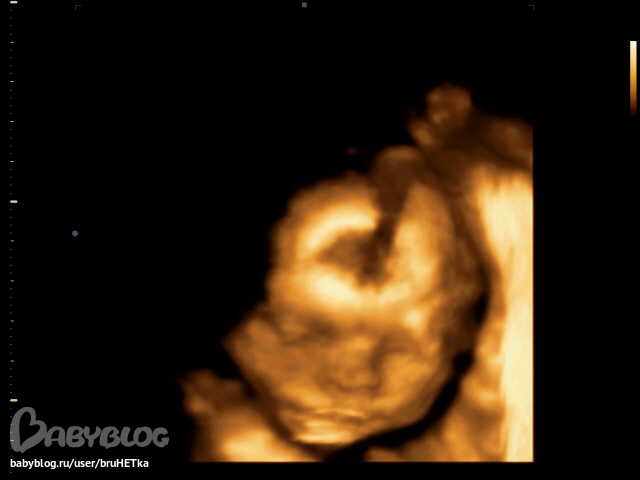

... Мы записали и видео и фото и не сколько об этом не жалеем... Гриша (так зовут сынулю) продемонстрировал нам все на что способен: и ручку в ротик запихал,

и зевнул (или что-то подобное), и глазки потер, и даже икал и все это на одном приеме УЗИ

. Счастью нет предела, это так умилительно посмотреть на пупса, когда он еще в пузике

. Он уже такой симпотичный прям человечище... Делюсь самой лучшей фоткой и всем-всем желаю счастья и удачи в начинаниях!!! Апчхишки на всех кому это требуется, держу за всех кулачки..